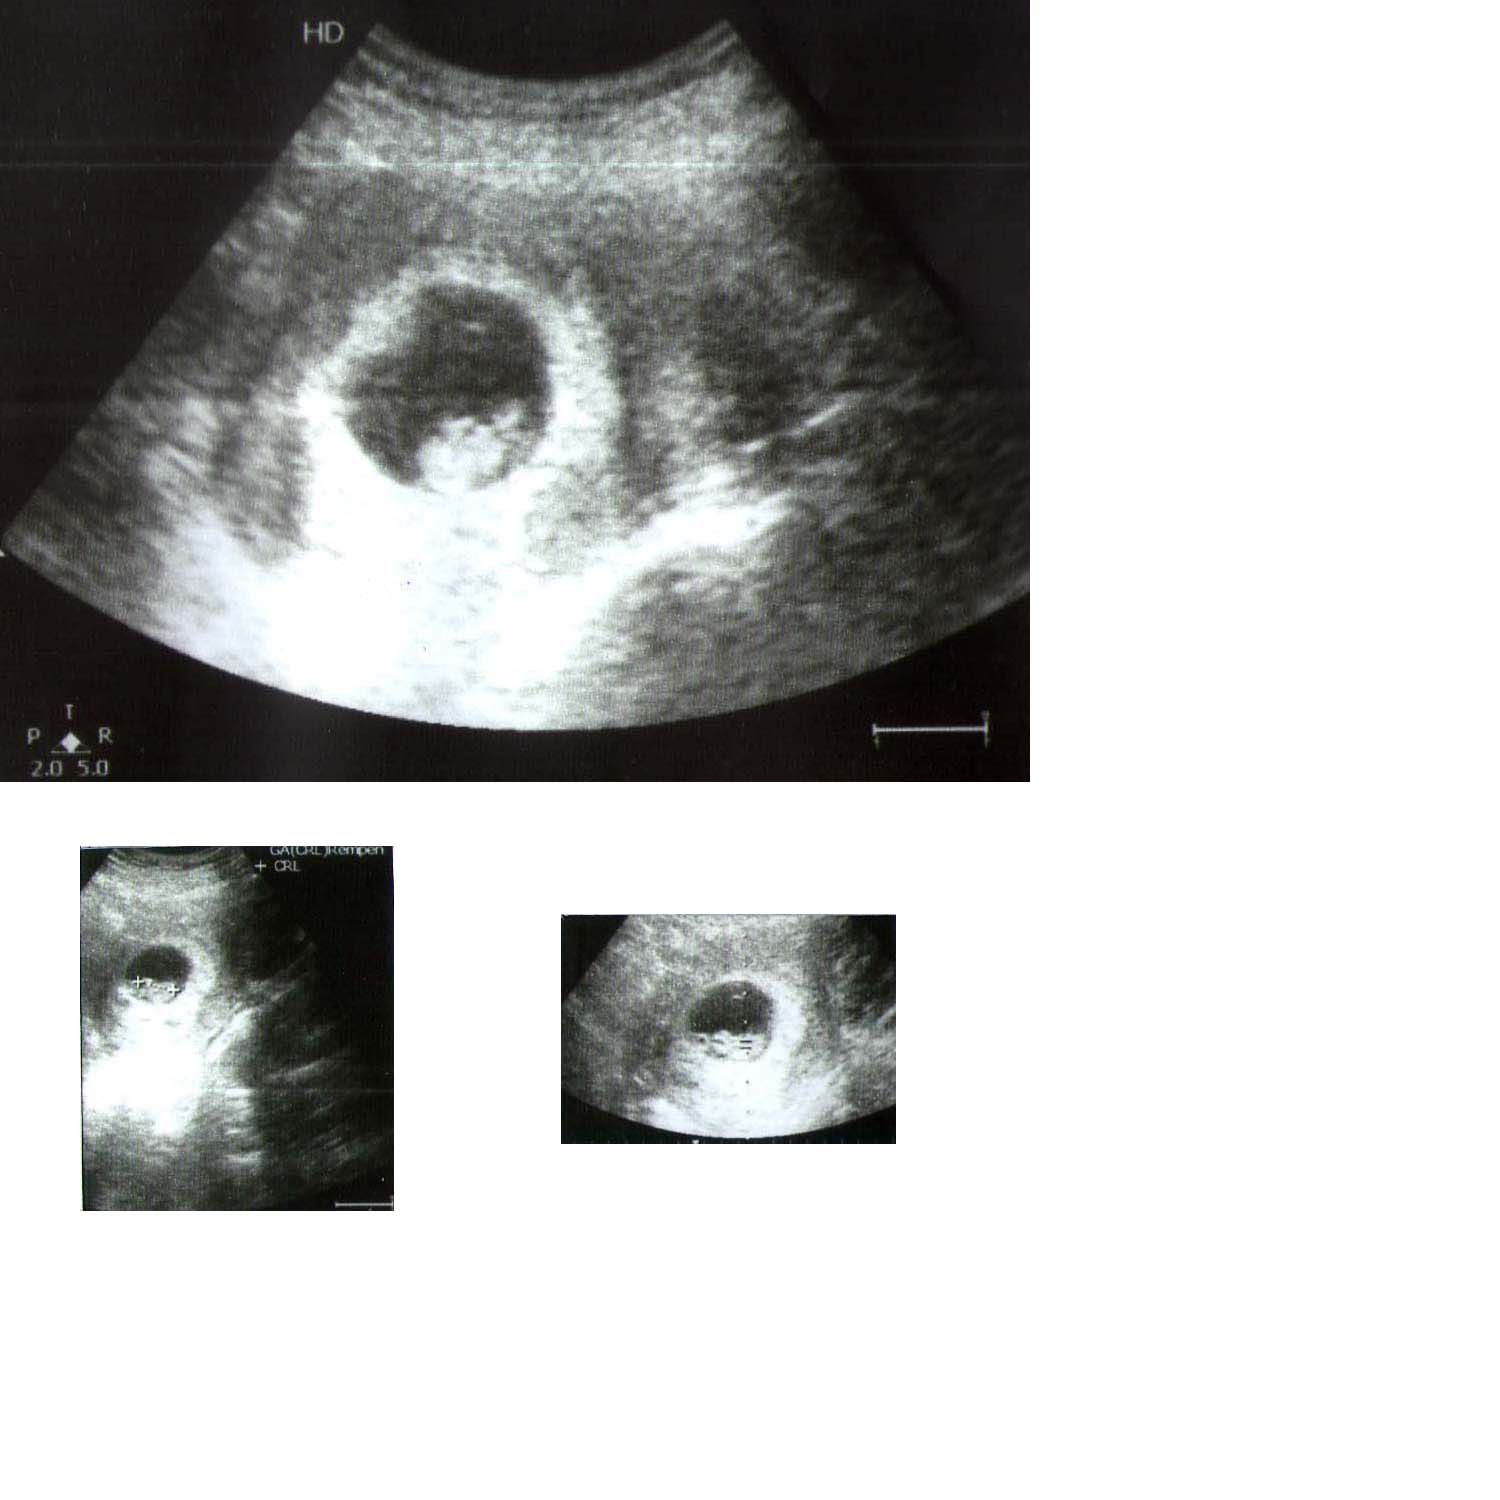

Dear Friends, Can you all guess from this pic. Pic attached is 8w3d and an normal abdominal scan. Placenta is posterior grade1 from my scan report.

Will post more pics of my 18 week scan soon.